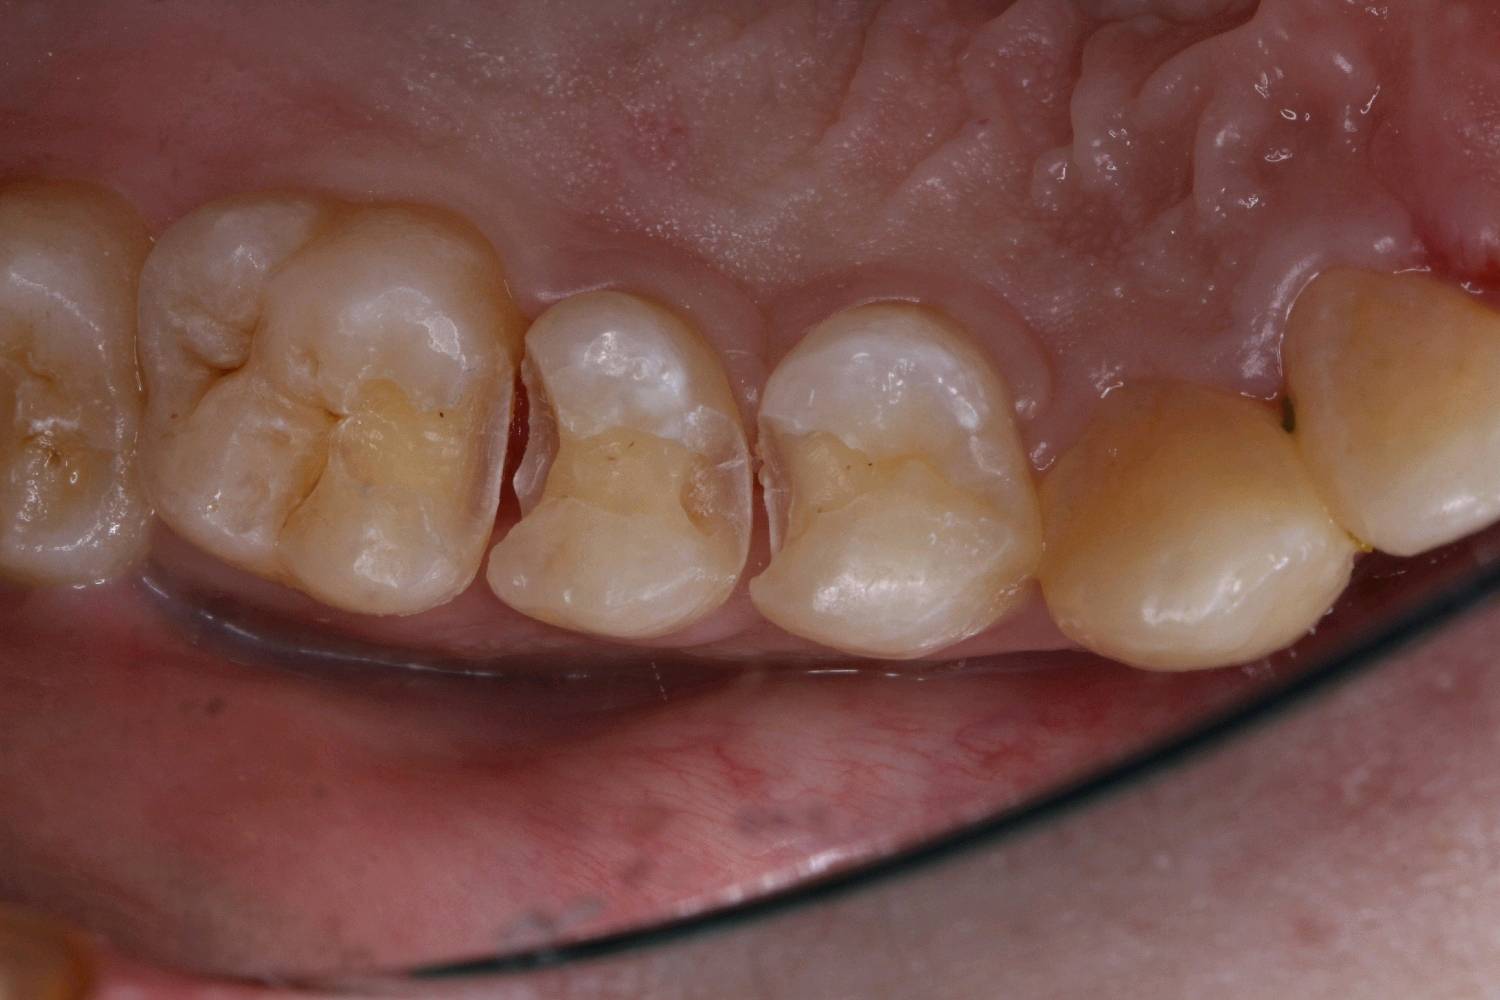

患者男24岁,自述右侧后牙食物嵌塞,无用牙线习惯。检查发现14,15,16,45,46 ,47邻颌面龋坏,探(-),扣(-),冷测正常,龋坏至牙本质中层,余无特殊。

治疗计划:嵌体修复

食物嵌塞为细菌提供了良好的滋生环境,容易导致细菌大量繁殖,产生酸性物质,从而增加蛀牙的风险。最好是用嵌体修复,能更好的恢复牙体的形态和功能。想要有一口好牙齿,做起来也不难。但是,单单口腔清洁这件小事,大多数人都没做好。你以为刷遍了牙齿的每个角落,但可能只刷了一半的牙。刷毛无法有效进入牙缝隙刷牙后仍有食物残渣等残留于牙齿邻面部位导致邻面龋坏。平时不易察觉,需要定期检查,为了更恢复邻接关系,预备制作嵌体,更好的恢复了牙体形态,增加了固位力,恢复正常的邻接关系,可以得到更好洁。基牙预备后,通过德国西诺德 CEREC ,当日完成即可佩戴,患者满意。